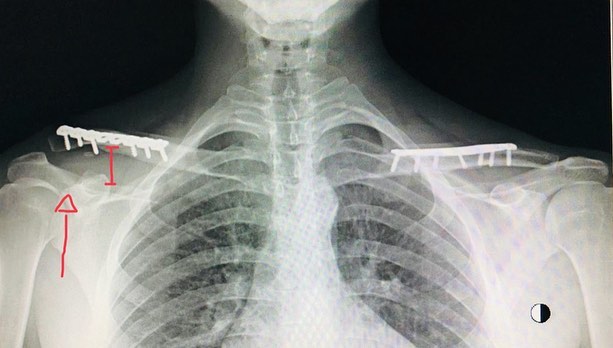

Micha: Muy bien!, me he mantenido muchos años como uno de los grandes exponentes de Chile en downhill y enduro, a pesar de tener muchas lesiones durante 3 años seguidos, 2 clavículas, 1 tobillo, 2 codos, y una muñeca, requiere mucha perseverancia recuperarse de tales lesiones y volver a tu rendimiento original, no requiere mucho esfuerzo por mi parte, así que me queda claro que es lo que amo.

Micha: desde que comencé hasta la temporada 2017 no me lesione mucho, pienso que fue por presionarme mucho, quise llevar mi juego a otro nivel, qué más es mejor, pero no es así, toque mi límite y tuve que pagar el precio, fue una lesion grave, me extirparon hueso del codo y me colocaron una prótesis de metal que reemplazara el hueso que era irreparable, hice todo muy bien, me recupere rápido, con muchas limitaciones de movilidad y fuerza, 6 meses después estaba 4to en el Andes Pacifico 2018 y 27 en el EWS de la parva 2018, 40 en el EWS de colombia, sin embargo en Agosto me fracture la Tibia y Perone en La Thuile, en mi primera incursión en terrenos Europeos. Desde ahí no me he lesionado y estoy mas fuerte que nunca, esperando el momento, para volver a probar en europa, la calidad y cantidad de lugares para andar son MAGISTRALES.